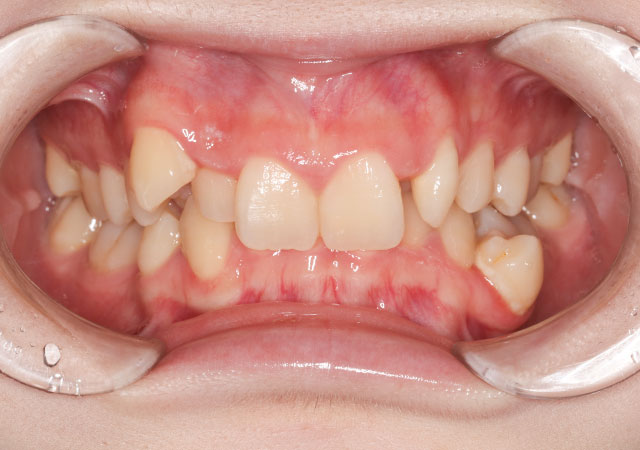

【治療内容】八重歯(叢生)の患者さんです。部分矯正(ホワイトワイヤー)で歯並びを治しました。

【費用】ホワイトワイヤー部分矯正 280,000円(税抜)

【リスク】矯正装置が口の中にあたって口内炎が出来やすくなる方もおられます。